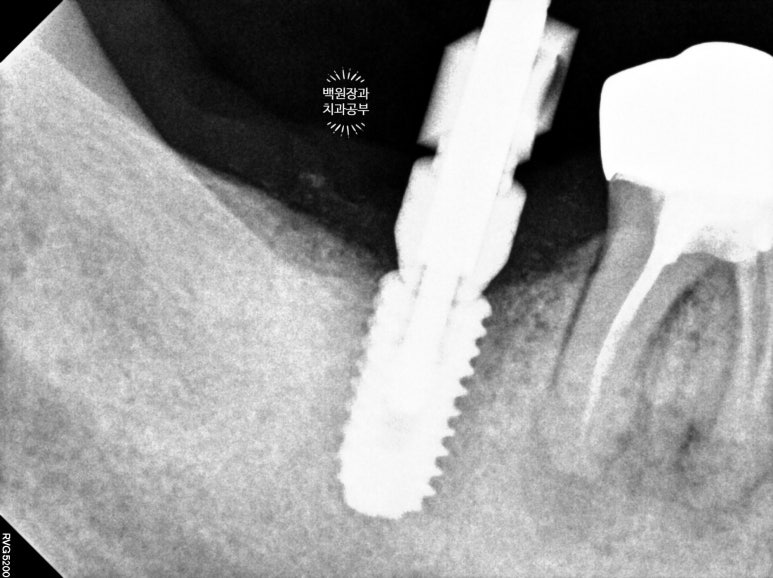

일단 임플란트를 정위치에 위치시키고, 오스템 임플란트를 사용하여 수술하였습니다.

부족한 부위는 합성뼈로 채워넣었습니다.

저희 연세더좋은플란트치과는 덴티움의 osteon III를 사용하고 있답니다!

그리고 같은 덴티움 사의 dentium collagen membrane (차폐막)을 이용하여 골이식재 상방을 덮어주었습니다.

제대로 된 뼈이식을 하려면 골이식재를 차폐막으로 무조건 덮어주어야 합니다! 말뿐인 골이식재가 아니라 확실한 결과를 얻기 위해선 학문적으로 차폐막의 사용은 필수입니다.

그리하여 수술 후 치과용 파노라마 사진입니다.

임플란트 위치가 아주 듬직하니 마음에 드네요!!